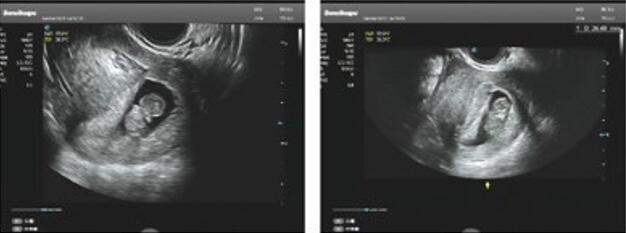

故,小苏按徐主任制定的来曲唑方案进行周期促排,周期医生王燕跟进促排超声监测,成功获卵12枚,形成4枚优质卵裂胚胎,1枚囊胚。

经过评估,王燕医生告知小苏不适合马上移植,因为超声发现子宫有异常情况,需先做宫腔镜检查明确诊断。

在徐士儒主任团队的助力下,小苏通过自然周期方案调理内膜,一切准备就绪,2023年2月,复苏冷冻移植1个囊胚,成功验得好孕,已于4月顺利产检“毕业”啦~